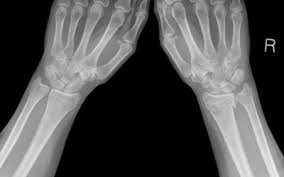

Some patients heal faster, some slower. Most people think of arthritis as painful joints. The radius and the ulna. If you have fracture that doesn't require surgery, you'll need to wear a sling for two to six weeks. However, while the bones usually take six to eight weeks to knit together, it may take up to a year for the arm to fully return to normal. Healing can range from 6 weeks or even less for certain lower arm and wrist fractures to 6 months for more challenging leg breaks. The elbow joint is a hinge type of joint composed of 3 bones. The time it takes you to recover from an upper arm and elbow fracture depends on the severity of the break.

Healing times vary greatly depending on the type of fracture you have. Healing can range from 6 weeks or even less for certain lower arm and wrist fractures to 6 months for more challenging leg breaks. While a fracture happens to one of the 3 bones, the most common cause is blunt impact on a hard surface or being struck with a solid object such as a baseball or bat. Whether you have gone through surgery or gotten a simple splint, this amount of time is usually enough for your bones to heal and for you to start using your elbow normally. Then go through physical therapy. The time it takes you to recover from an upper arm and elbow fracture depends on the severity of the break. In most cases, the swelling reduces — and you will probably feel better — after a couple of days. And that's with or without surgery. However, the elbow is a joint so, as a space, you really can't break it. Complete healing takes a year. Malunion occurs when healing bones grow back together in an abnormal. Recovery from an elbow fracture following treatment for an elbow fracture, most children remain in a cast for about four weeks. For some, full healing can take up to a year after injury.